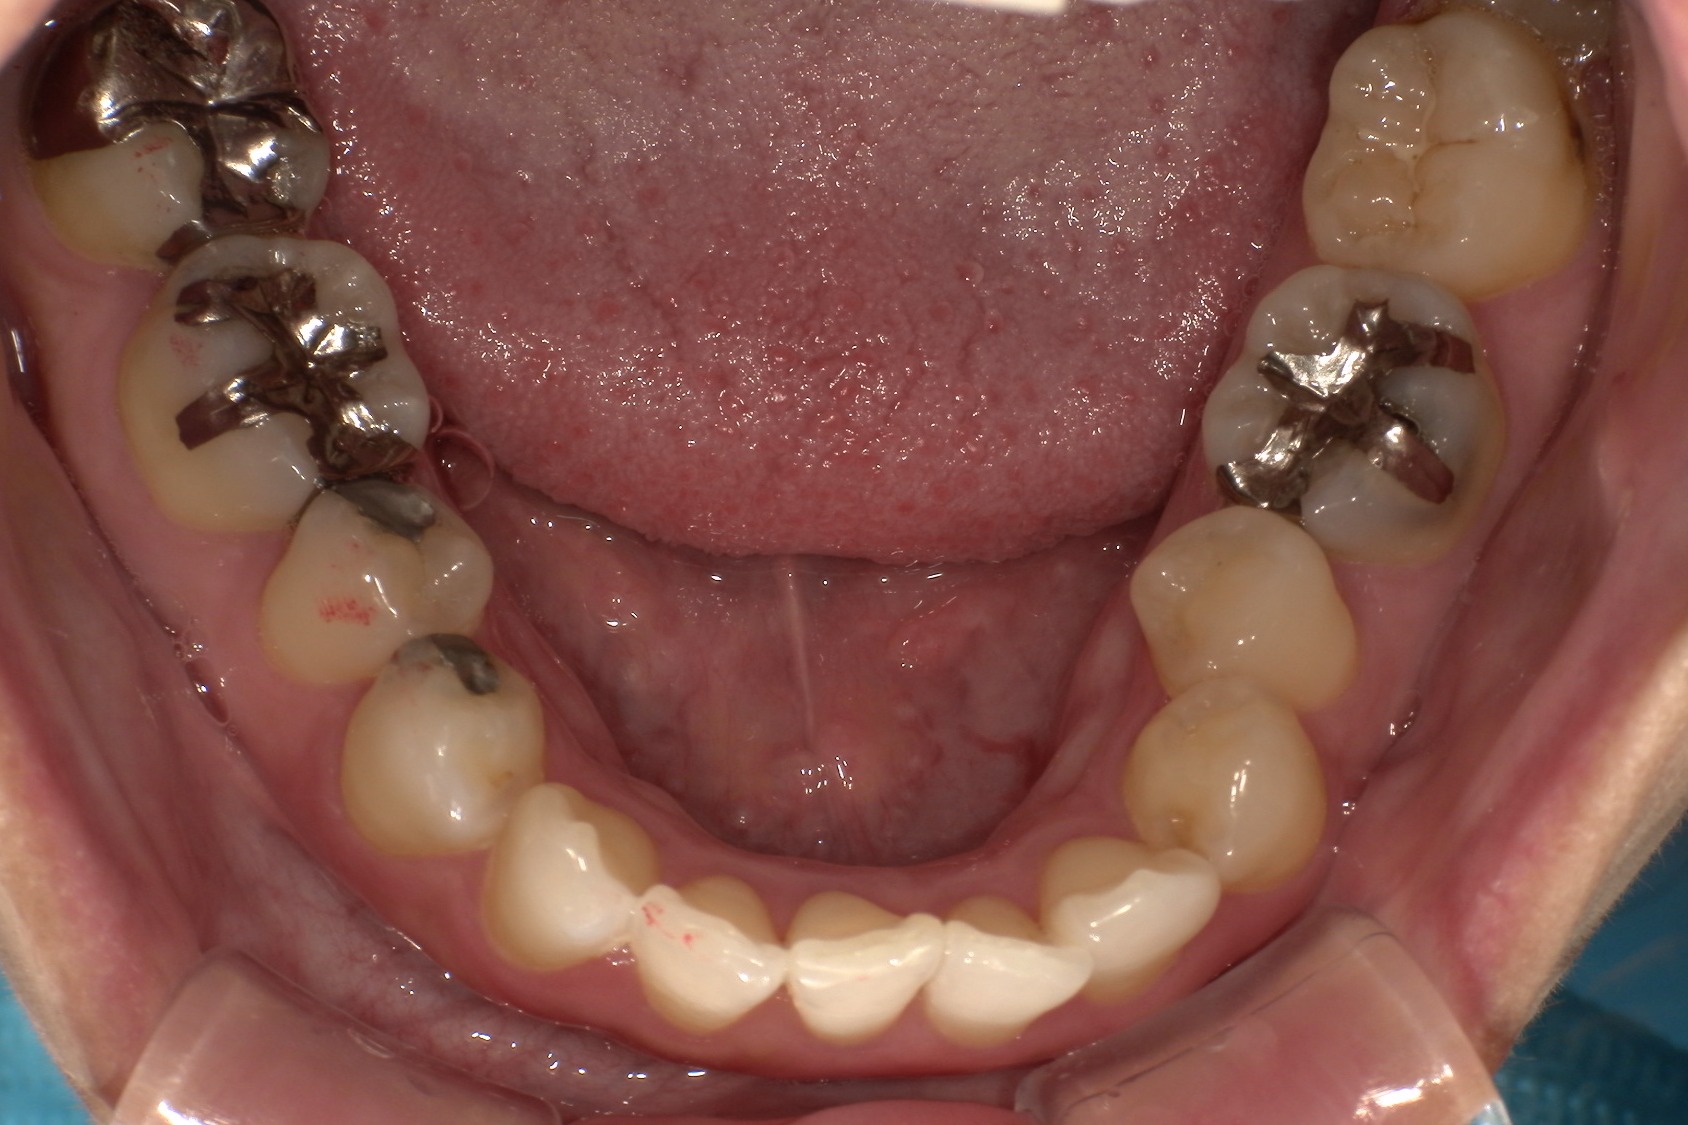

毎週自分で歯並びの写真を撮っていたので日々綺麗になっていく歯並びを見るのが嬉しく、家族からも綺麗になったねと言われました! マウスピース矯正と並行してホワイトニングも行っていたので、歯が格段に綺麗になるのを実感できたのが嬉しかったです。